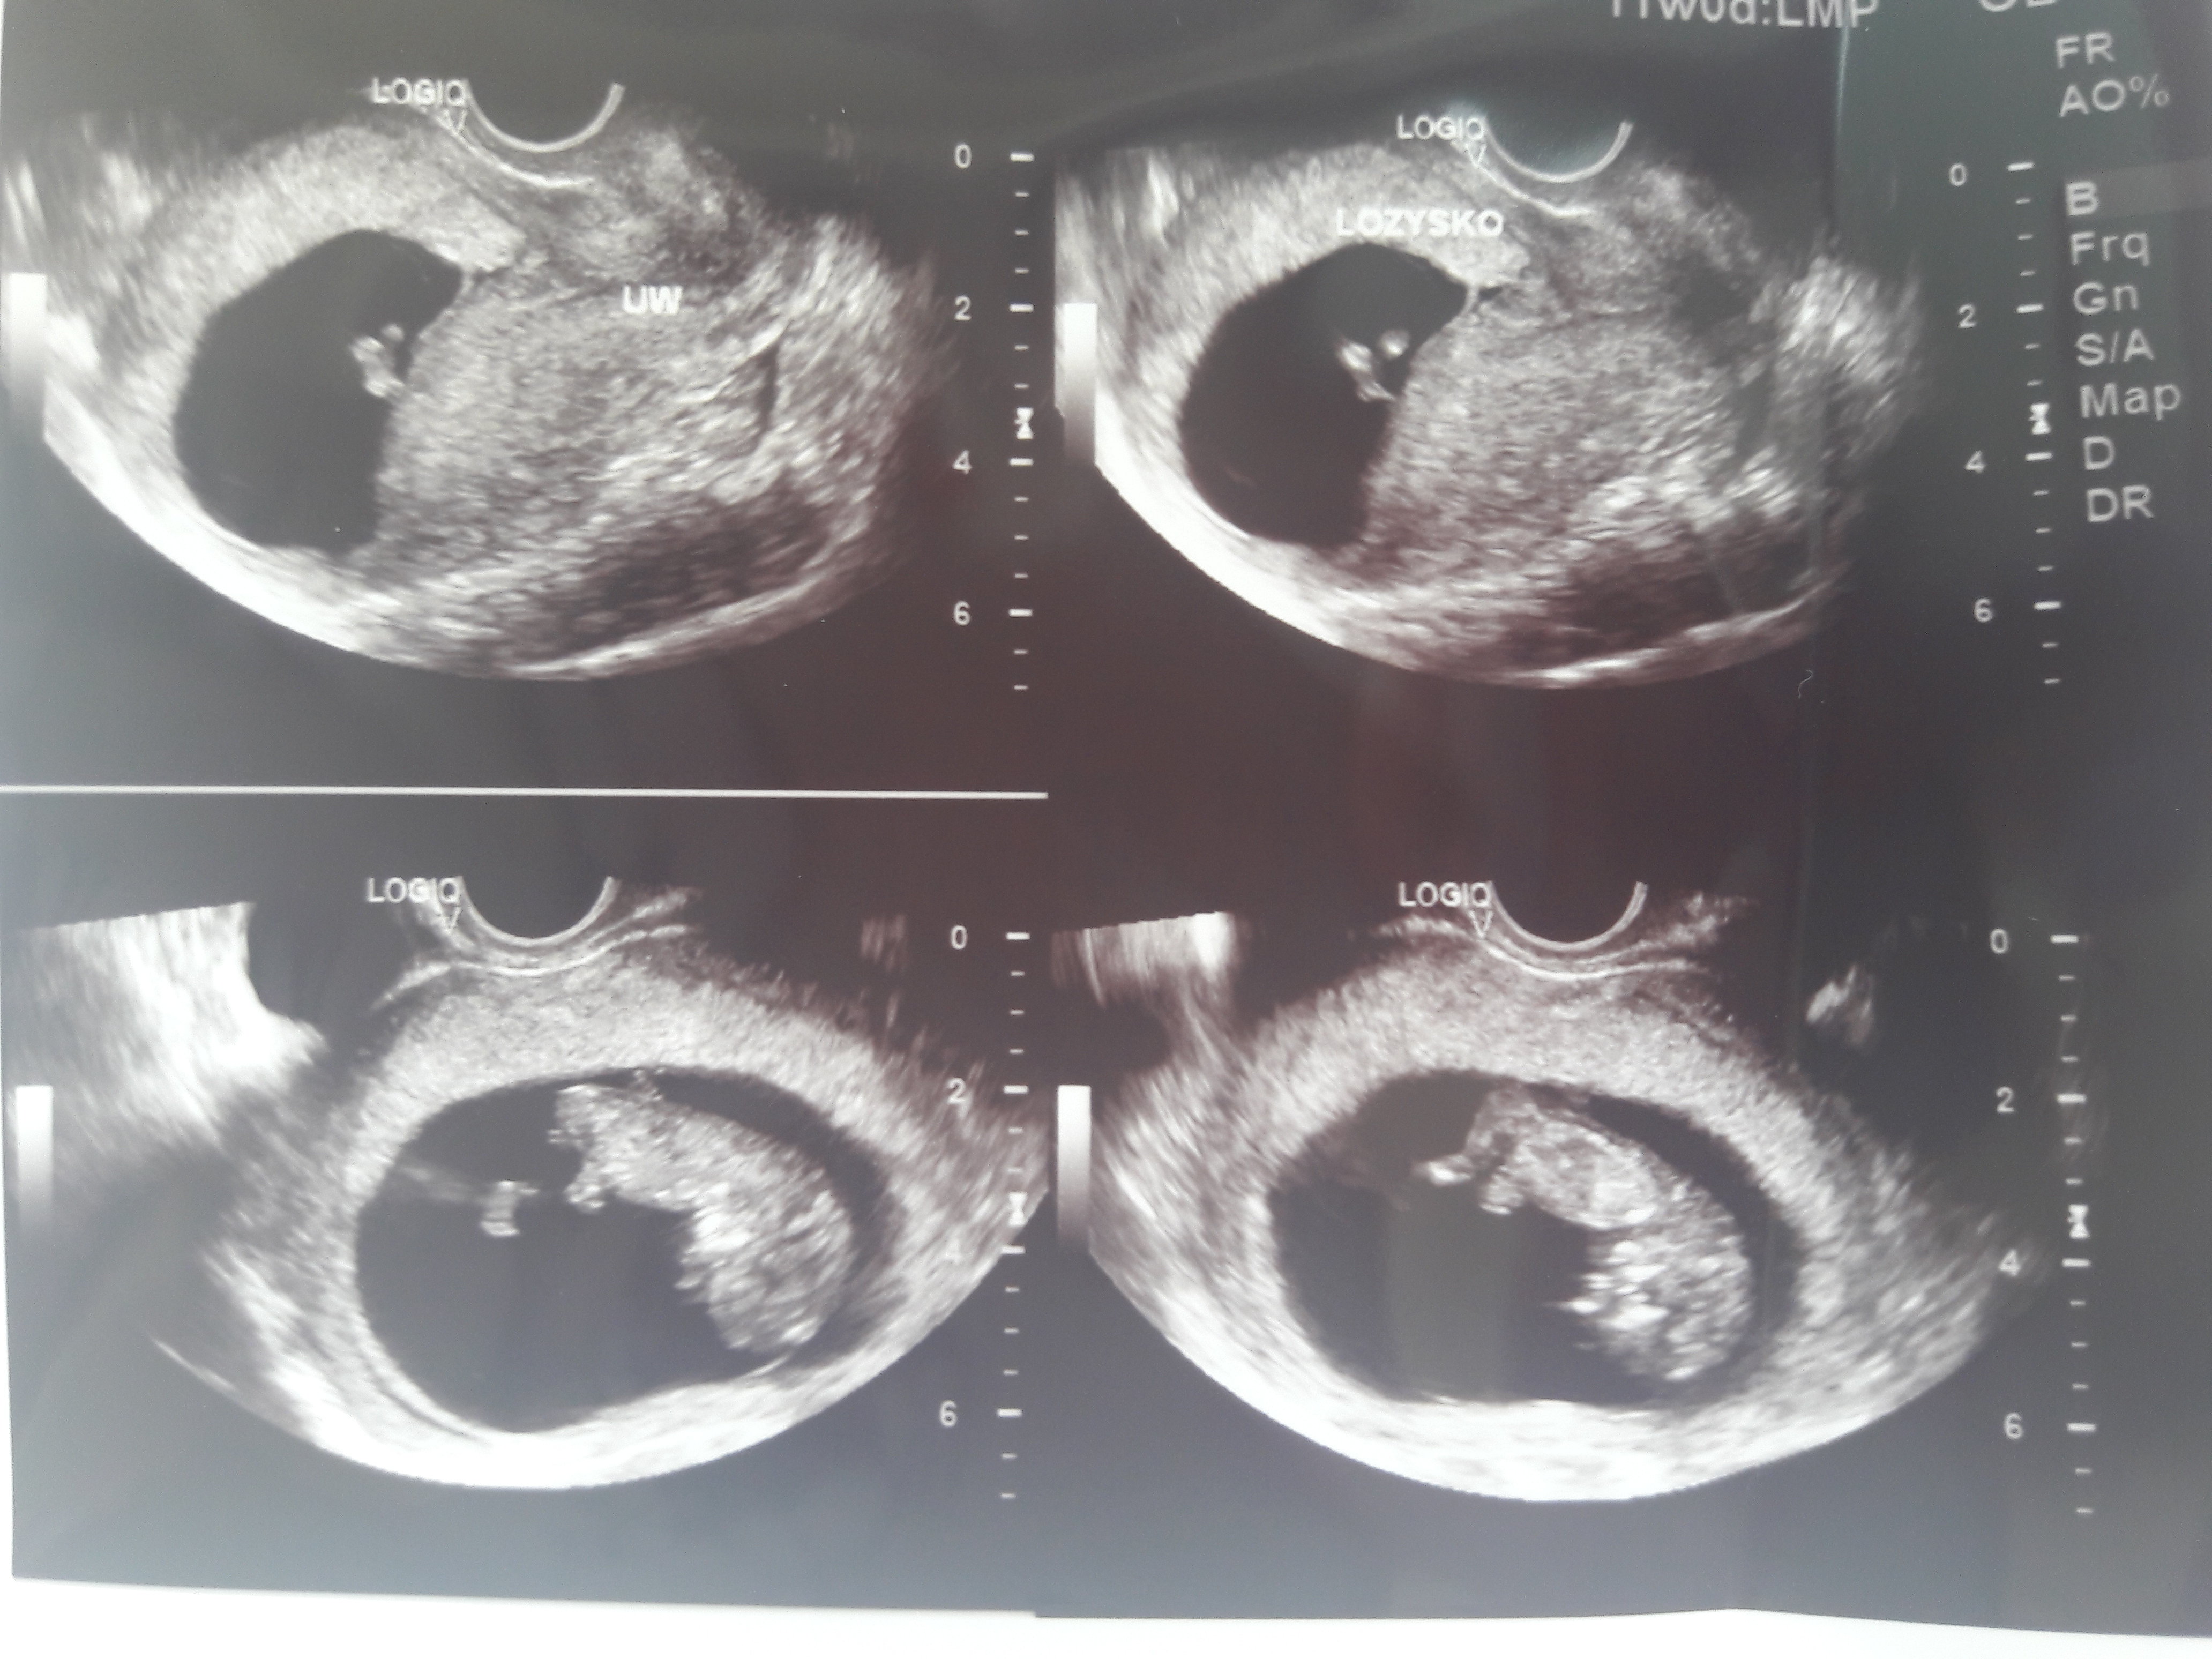

ja już po wizycie :) wg usg. 10+3, wg miesiaczki 11+1. Dzidziuś urosł przez 2 tygodnie z 2,2cm na 4,1cm. fikał dziś koziołki ,byl dzis jakis szalony i zdjęcia jakies mało wyrazne... Lozysko dalej przykrywa ujscie szyjki , dalej musze polegiwać i sie mocno oszczedzac. kolejna wizyta za 3 tyg ale za 2 tyg badania prenatalne :) Stres schodzi, wazne ze dzidzia rosnie a teraz do polegujących- czy te Wasze seriale mozna obejrzec bez Netflixa ? niestety nie mam... siedze na tvnplayer ale chyba oszaleje :)

Calkiem wyrazne te zdjecia i pieknie juz ksztalty widac :)